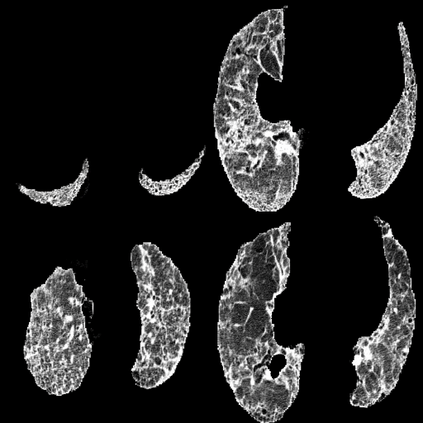

In the field of medical imaging, particularly in tasks related to early disease detection and prognosis, understanding the reasoning behind AI model predictions is imperative for assessing their reliability. Conventional explanation methods encounter challenges in identifying decisive features in medical image classifications, especially when discriminative features are subtle or not immediately evident. To address this limitation, we propose an agent model capable of generating counterfactual images that prompt different decisions when plugged into a black box model. By employing this agent model, we can uncover influential image patterns that impact the black model's final predictions. Through our methodology, we efficiently identify features that influence decisions of the deep black box. We validated our approach in the rigorous domain of medical prognosis tasks, showcasing its efficacy and potential to enhance the reliability of deep learning models in medical image classification compared to existing interpretation methods. The code will be publicly available at https://github.com/ayanglab/DiffExplainer.